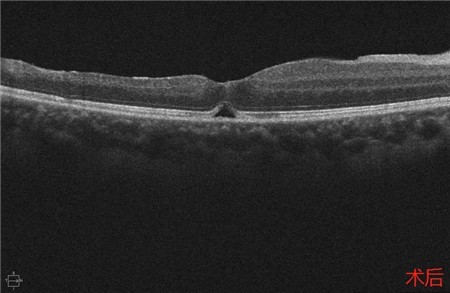

经过详细的眼底检查后,患者被诊断为IRVAN综合征引起的右眼黄斑裂孔,张风院长带领医生团队为患者施局右眼玻璃体切除+剥膜+眼内光凝+气液交换手术,经过半个月的恢复,患者右眼术后视力由术前0.3-达到0.6-的状态,且裂孔呈逐渐闭合状态。

视盘附近的动脉和动脉分叉处出现瘤样动脉扩张,视盘充血,边界不清,引起视盘周围视网膜内硬性渗出;视盘周可有少量放射状出血。

静脉不规则扩张和血管鞘膜,周边部小血管广泛闭塞,交界处毛细血管扩张和异常吻合。

严重者可发生从周边到黄斑的血管闭塞和缺血、玻血、新生血管性青光眼,最终视神经萎缩。